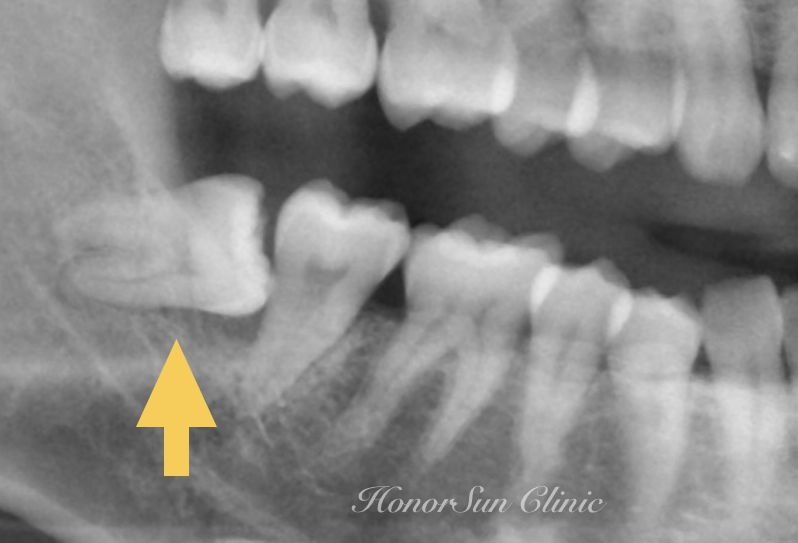

智齒造成鄰牙蛀牙

現代人的精緻飲食,柔軟的食物沒有刺激牙弓持續擴大,因此常出現最後生長的智齒沒有空間排列的情形。長歪、卡住的阻生智齒,形成清潔的死角,往往會出現牙齦腫脹、蛀牙、牙周病等狀況。